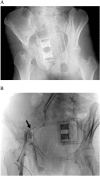

Pelvic circumferential compression devices (PCCDs) have gained wide acceptance in the management of patients with pelvic fracture. These devices are considered safe due to their noninvasive nature and significant hazards associated with the use of PCCDs have not been reported previously. However, we present herein the cases of three patients who received PCCD application and eventually developed major complications presumably caused by PCCDs. As a result, one patient developed surgical site infection following internal fixation and required several debridements. Another patient ended up with a walking disability. The remaining patient eventually died from exsanguination following application of the PCCD. Clinicians should be aware of the potential for deleterious effects, including bladder rupture, muscle necrosis, and vessel injuries. In particular, application for acetabular fractures and prolonged application of PCCDs should be avoided.